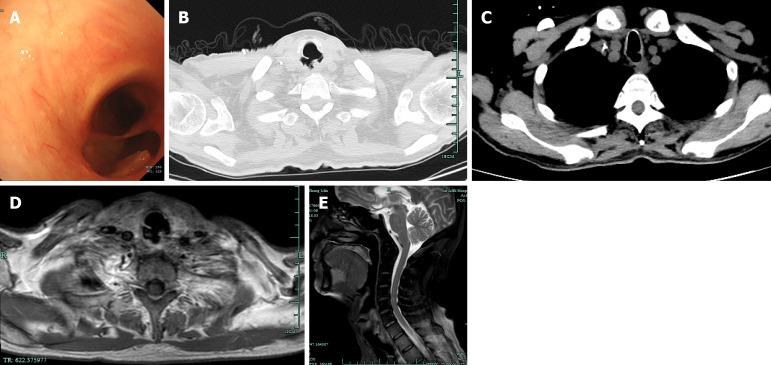

CASE SUMMARY

Here, we present a 59-year-old male patient with a 5-month history of CEC and difficulty eating for over 20 days, who developed TEF secondary to recurrent ESCC after chemoradiotherapy. He underwent total pharyngolaryngoesophagectomy, left thyroidectomy, and lymphadenectomy. Gastric pull-up was performed to restore gastrointestinal continuity, and a 7 cm × 5 cm supraclavicular artery island flap (SCAIF) was used to reconstruct the lower tracheal defect. Despite severe postoperative complications, he recovered by successful management by a MDT. A 7 cm × 6 cm pectoralis major myocutaneous flap was successfully used to repair the necrotic gastric conduit defect. The patient recovered, regaining the ability to eat and breathe effectively. At the 27-month follow-up, he was alive without recurrence or metastasis.

在此,我们报告一名59岁男性患者,有5个月的CEC病史,进食困难超过20天,在放化疗后因复发性ESCC继发TEF。他接受了全喉咽食管切除术、左侧甲状腺切除术和淋巴结清扫术。进行了胃上提术以恢复胃肠道连续性,并使用一块7厘米×5厘米的锁骨下动脉岛状皮瓣(SCAIF)修复气管下段缺损。尽管术后出现严重并发症,但通过MDT的成功管理,他得以康复。一块7厘米×6厘米的胸大肌肌皮瓣成功用于修复坏死的胃管道缺损。患者康复,恢复了有效进食和呼吸的能力。在27个月的随访中,他存活且无复发或转移。